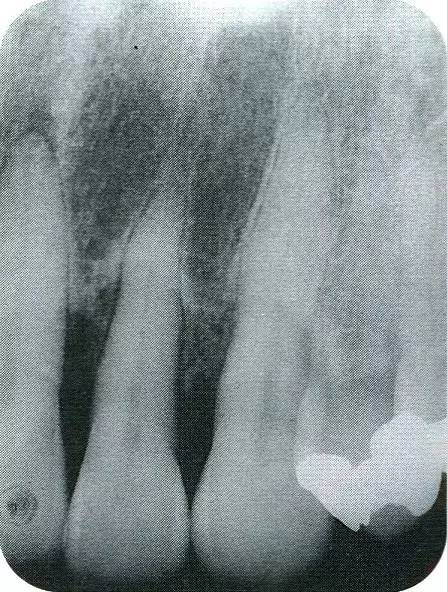

▲圖7-2  術(shù)前x片。確認(rèn)存在垂直性深骨缺損。